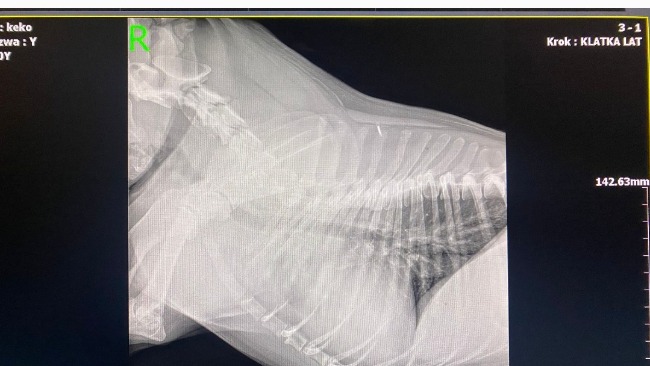

Od tego momentu zostało wykonane RTG, liczne USG, badania krwi, Echo serca...i w koncu TK z kontrastem, które niestety potwierdziło bardzo smutną dla mnie diagnozę...guz podstawy serca💔

Guz o średnicy 4,5 cm uciska mu aortę i tchawicę. Niestety są już także przerzuty w węzłach chłonnych śródpiersia.

Pomimo tak strasznej diagnozy, Keko jest w dobrej kondycji klinicznej, ma apetyt i uwielbia spacery, coprawda już w swoim własnym tempie, bo ma nadciśnienie płucne i zadyszkę, przez ucisk guza na tchawicę i płuca.